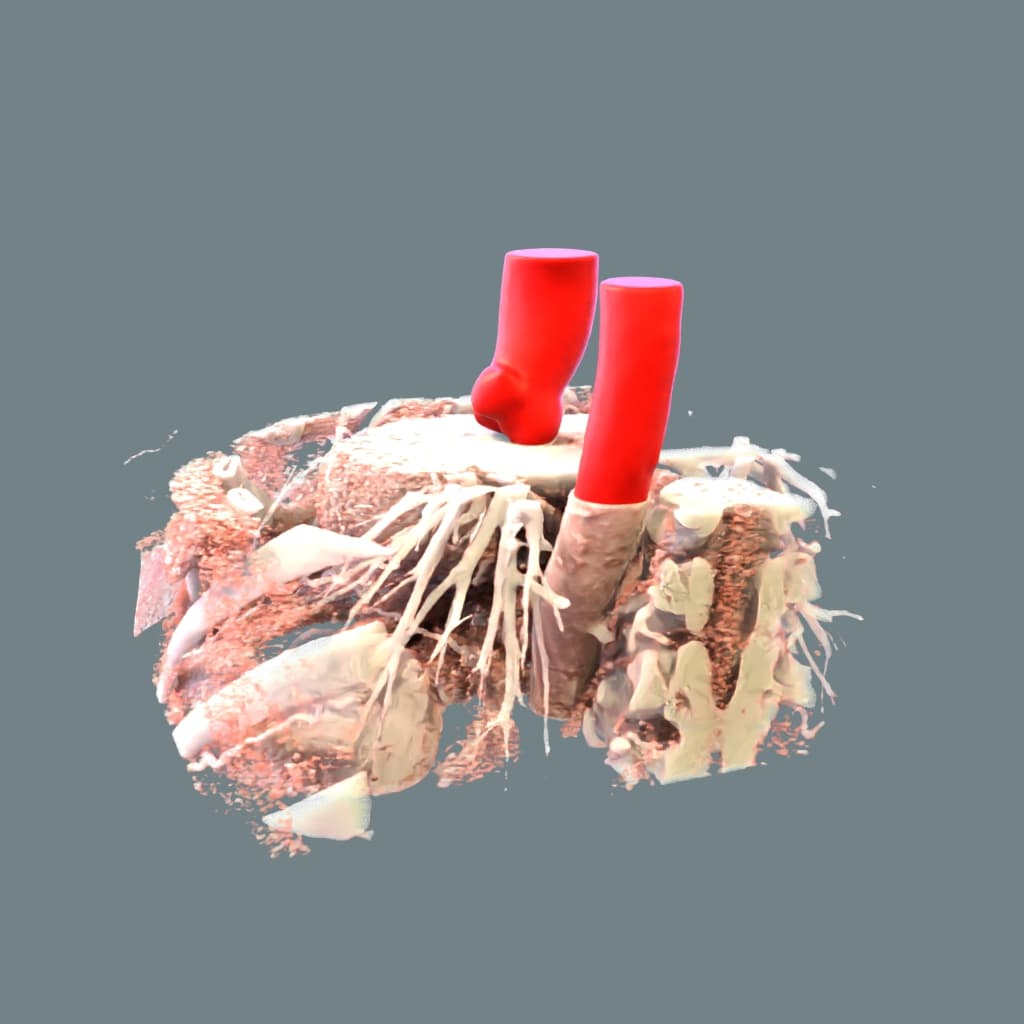

Contrast-enhanced CT images are the preferred method for the assessment of thoracic aorta including visualization of pathologies (e.g. aortic aneurysm*) and measurement of diameters at specific levels. Moreover, accurate segmentation and visualization of aortic root is of special interest in cardiac CT imaging. Aortic root is the proximal portion of ascending aorta beginning at the level of aortic annulus and extending to sinotubular junction. Between each commissure of the aortic valve there are usually three aortic sinuses.

Automatic detection of the aortic root is an important element for further AI data processing. The difficulty in automatically segmenting the aortic root is twofold. Firstly, the aortic valve is poorly visible and classical methods of segmentation based on thresholding usually fail. Secondly, the valve can be opened and then the contrast connects directly to the left ventricle. In both cases, radiologists and cardiologists can rely on the general anatomical features of aortic sinuses/aortic annulus to extrapolate the location of a poorly visible aortic valve. The challenge is to create an algorithm that incorporates this intuition and correctly segments the aortic root in both cases.

ML generated segmentation of thoracic aorta. Note the accurate segmentation of aortic cusps.

Here we developed an AI algorithm for the segmentation of the thoracic aorta on contrast-enhanced cardiac CT images. The average Sørensen-Dice [1] coefficient of the model was above 0.98. The model is robust across images of different quality and produces meaningful results even in the case of open valve.